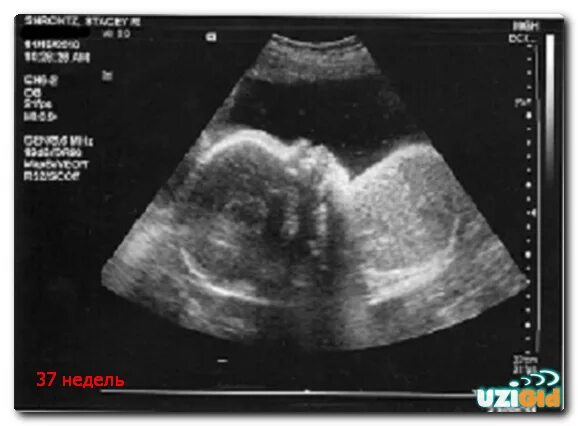

37 неделя беременности что происходит с малышом